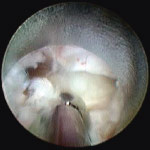

bandscheibe_endoskopsicht_1

Abb. 3

Durch das Endoskop wird die gelbliche Vorfallmasse sichtbar. Oben ist sichelförmig der seitliche Rand der zu schonenden Nervenscheide erkennbar.

bandscheibe_endoskopsicht_2

Abb. 4

Abtragung des Vorfallmaterials. Links oben am Rand die Nervenscheide, rechts rötlich einkragende Muskelfasern.